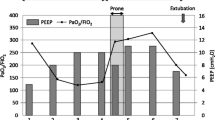

The cardiac surgeons consulted the intensive care doctors on day 4 regarding mechanical ventilation. The patient was in septic shock and was treated with a continuous infusion of epinephrine 0.15 μg/kg/min and norepinephrine 0.2 μg/kg/min (Fig. 1). As her hypoxemia and progressive hypercapnia had reached critical levels, we switched to inverse-ratio ventilation with an inspiratory-to-expiratory ratio of 2:1, inspiratory pressure of 34 cmH2O, PEEP of 18 cmH2O, and a ventilatory frequency of 31/min in order to increase minute ventilation without decreasing plateau pressure. Although the P/F ratio had stabilized (not worsened), the respiratory acidosis remained as indicated with PaCO2 at 62.9 mmHg and pH 7.209, respectively. Transthoracic echocardiography revealed severe RV dilatation (ratio between the RV and left ventricle [LV] end-diastolic areas was >1:1) in a four-chamber view, a paradoxical septal shift to the LV in the short-axis view, and severe tricuspid regurgitation, which were compatible with ACP [9]. The RV systolic pressure was estimated at >60 mmHg. The use of extracorporeal life support was excluded by the cardiac surgeons based on their expert opinion.

The following day, the patient’s gas distribution had completely returned to baseline level. At 4 h after prone positioning was started, EIT imaging confirmed the presence of homogeneous gas distribution in almost all areas. Approximately 64 % of the gas was distributed in the mid-dorsal and dorsal layers (Fig. 2, right), in accordance with the increase in the P/F to 334 mmHg. The RV systolic pressure was estimated at 41 mmHg at 7 h after the end of prone positioning. Although the hemodynamics remained stabilized until day 9, airway pressures could not be reduced because of instability while the patient remained supine. Alveolar instability was observed as dorsal derecruitment on EIT with a PaO2 reduction from 434 to 195 mmHg. We switched to APRV with a P high of 26 cmH2O on day 10 to decrease the plateau pressure but maintain mean airway pressure. P high was determined at the lowest PEEP to maintain dorsal recruitment as seen by EIT. Prone positioning was continued for 14 days for periods of <7 h at each session (Fig. 4). No adverse effects associated with prone positioning or EIT imaging were observed. The patient was weaned from mechanical ventilation on day 32 and was discharged on day 200.

Time course of PaO2/FIO2 ratio, PaCO2, and ventilator settings at specific events and interventions. A/C assist/control mode, APRV airway pressure release ventilation, IRV inverse-ratio ventilation, Paw airway pressure (peak/PEEP in A/C and IRV, Phigh/Plow in APRV), TTE transthoracic echocardiography, CHDF continuous hemodiafiltration